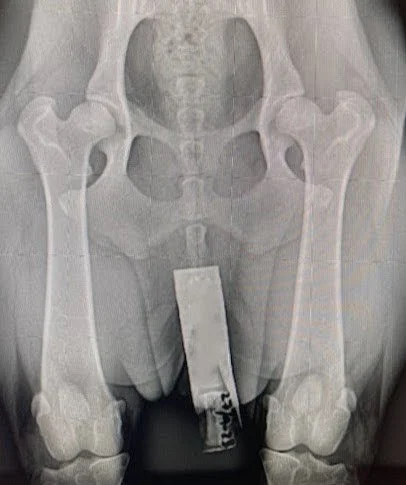

Rasen är generellt sett frisk. Det finns dock vissa hälsoundersökningar som är viktiga för alla fieldägare att genomföra för att bevara rasens goda hälsa även i framtiden. Läs mer om rasens hälsa, vilka hälsotester du som fieldägare bör göra samt vilka tester som rekommenderas för hundar som ska användas i avel.